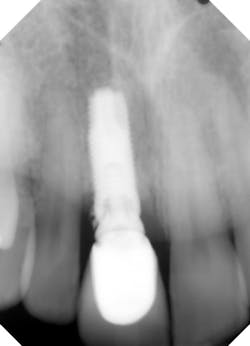

3. Tissue interferences, such as gingiva and/or bone between the abutment and fixture platform, should always be considered (especially in the posterior mandible) when misfit occurs. In addition, calculus, cement, and grafting material can also be lodge between mating surfaces of the abutment and fixture, and prevent seating (figure 2).